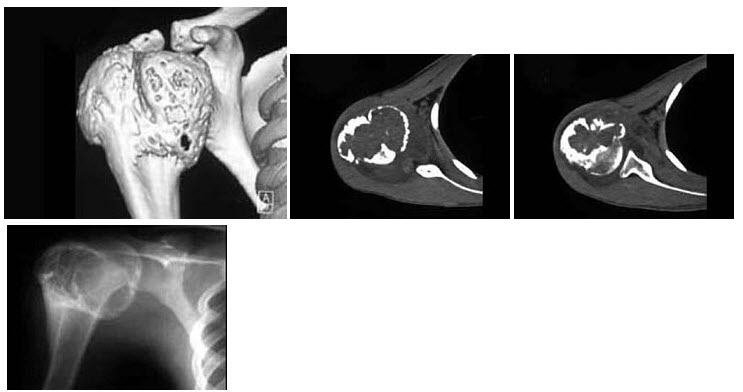

168、单项选择题

男,33岁,右肩部疼痛,巨大肿块,活动受限,结合图像,最可能的诊断是()

A.骨肉瘤

B.软骨瘤

C.骨软骨瘤

D.软骨肉瘤

E.骨转移瘤